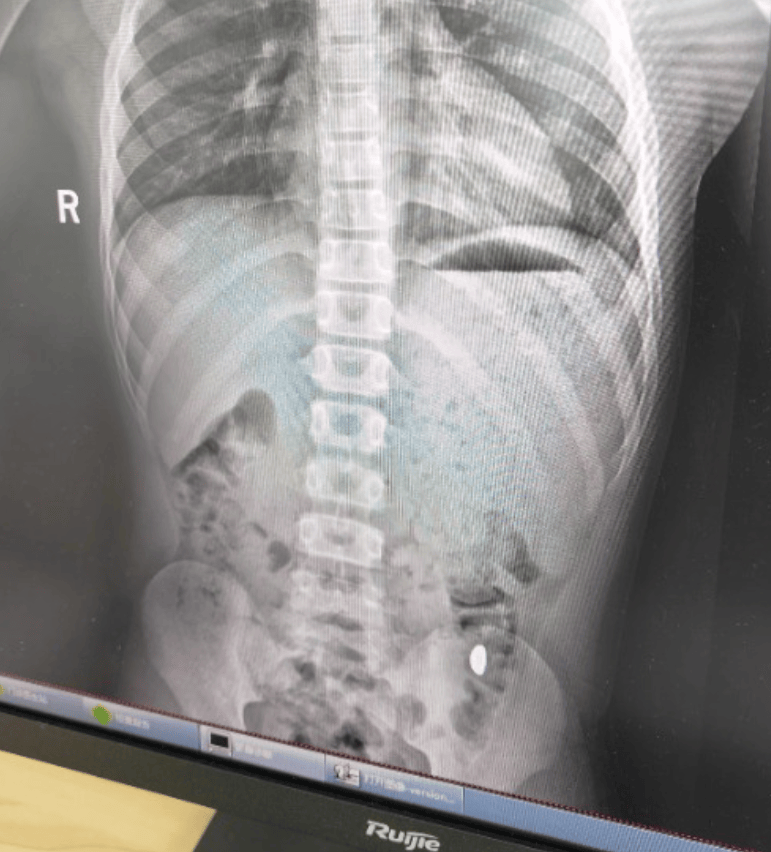

昆山市第五人民医院门诊病历单显示,患儿5天前误吞约10克黄金,其间解两次大便未发现,无腹痛、呕吐等症状,诊断结果显示胃内有异物。

右下加亮点为金豆。